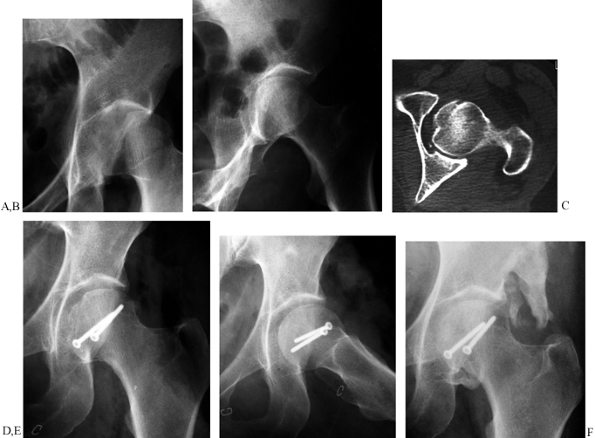

Percutaneous fixation of moderately displaced (2–5 mm) acetabular

fractures may not improve the reduction and often provides

less-than-optimal fixation. Percutaneous fixation has also been used in

nondisplaced fractures to allow early patient mobilization (58).

In our experience, patients with nondisplaced acetabular fractures can

be moved from bed to chair without risk of significant displacement.

Percutaneous fixation techniques may have potential benefits, but at

this time definitive indications for percutaneous fixation have not

been developed.